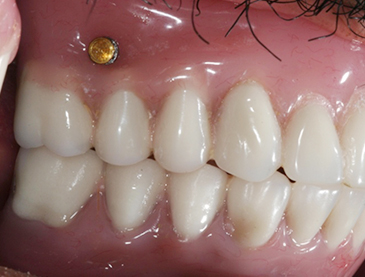

Fully edentulous clinical cases